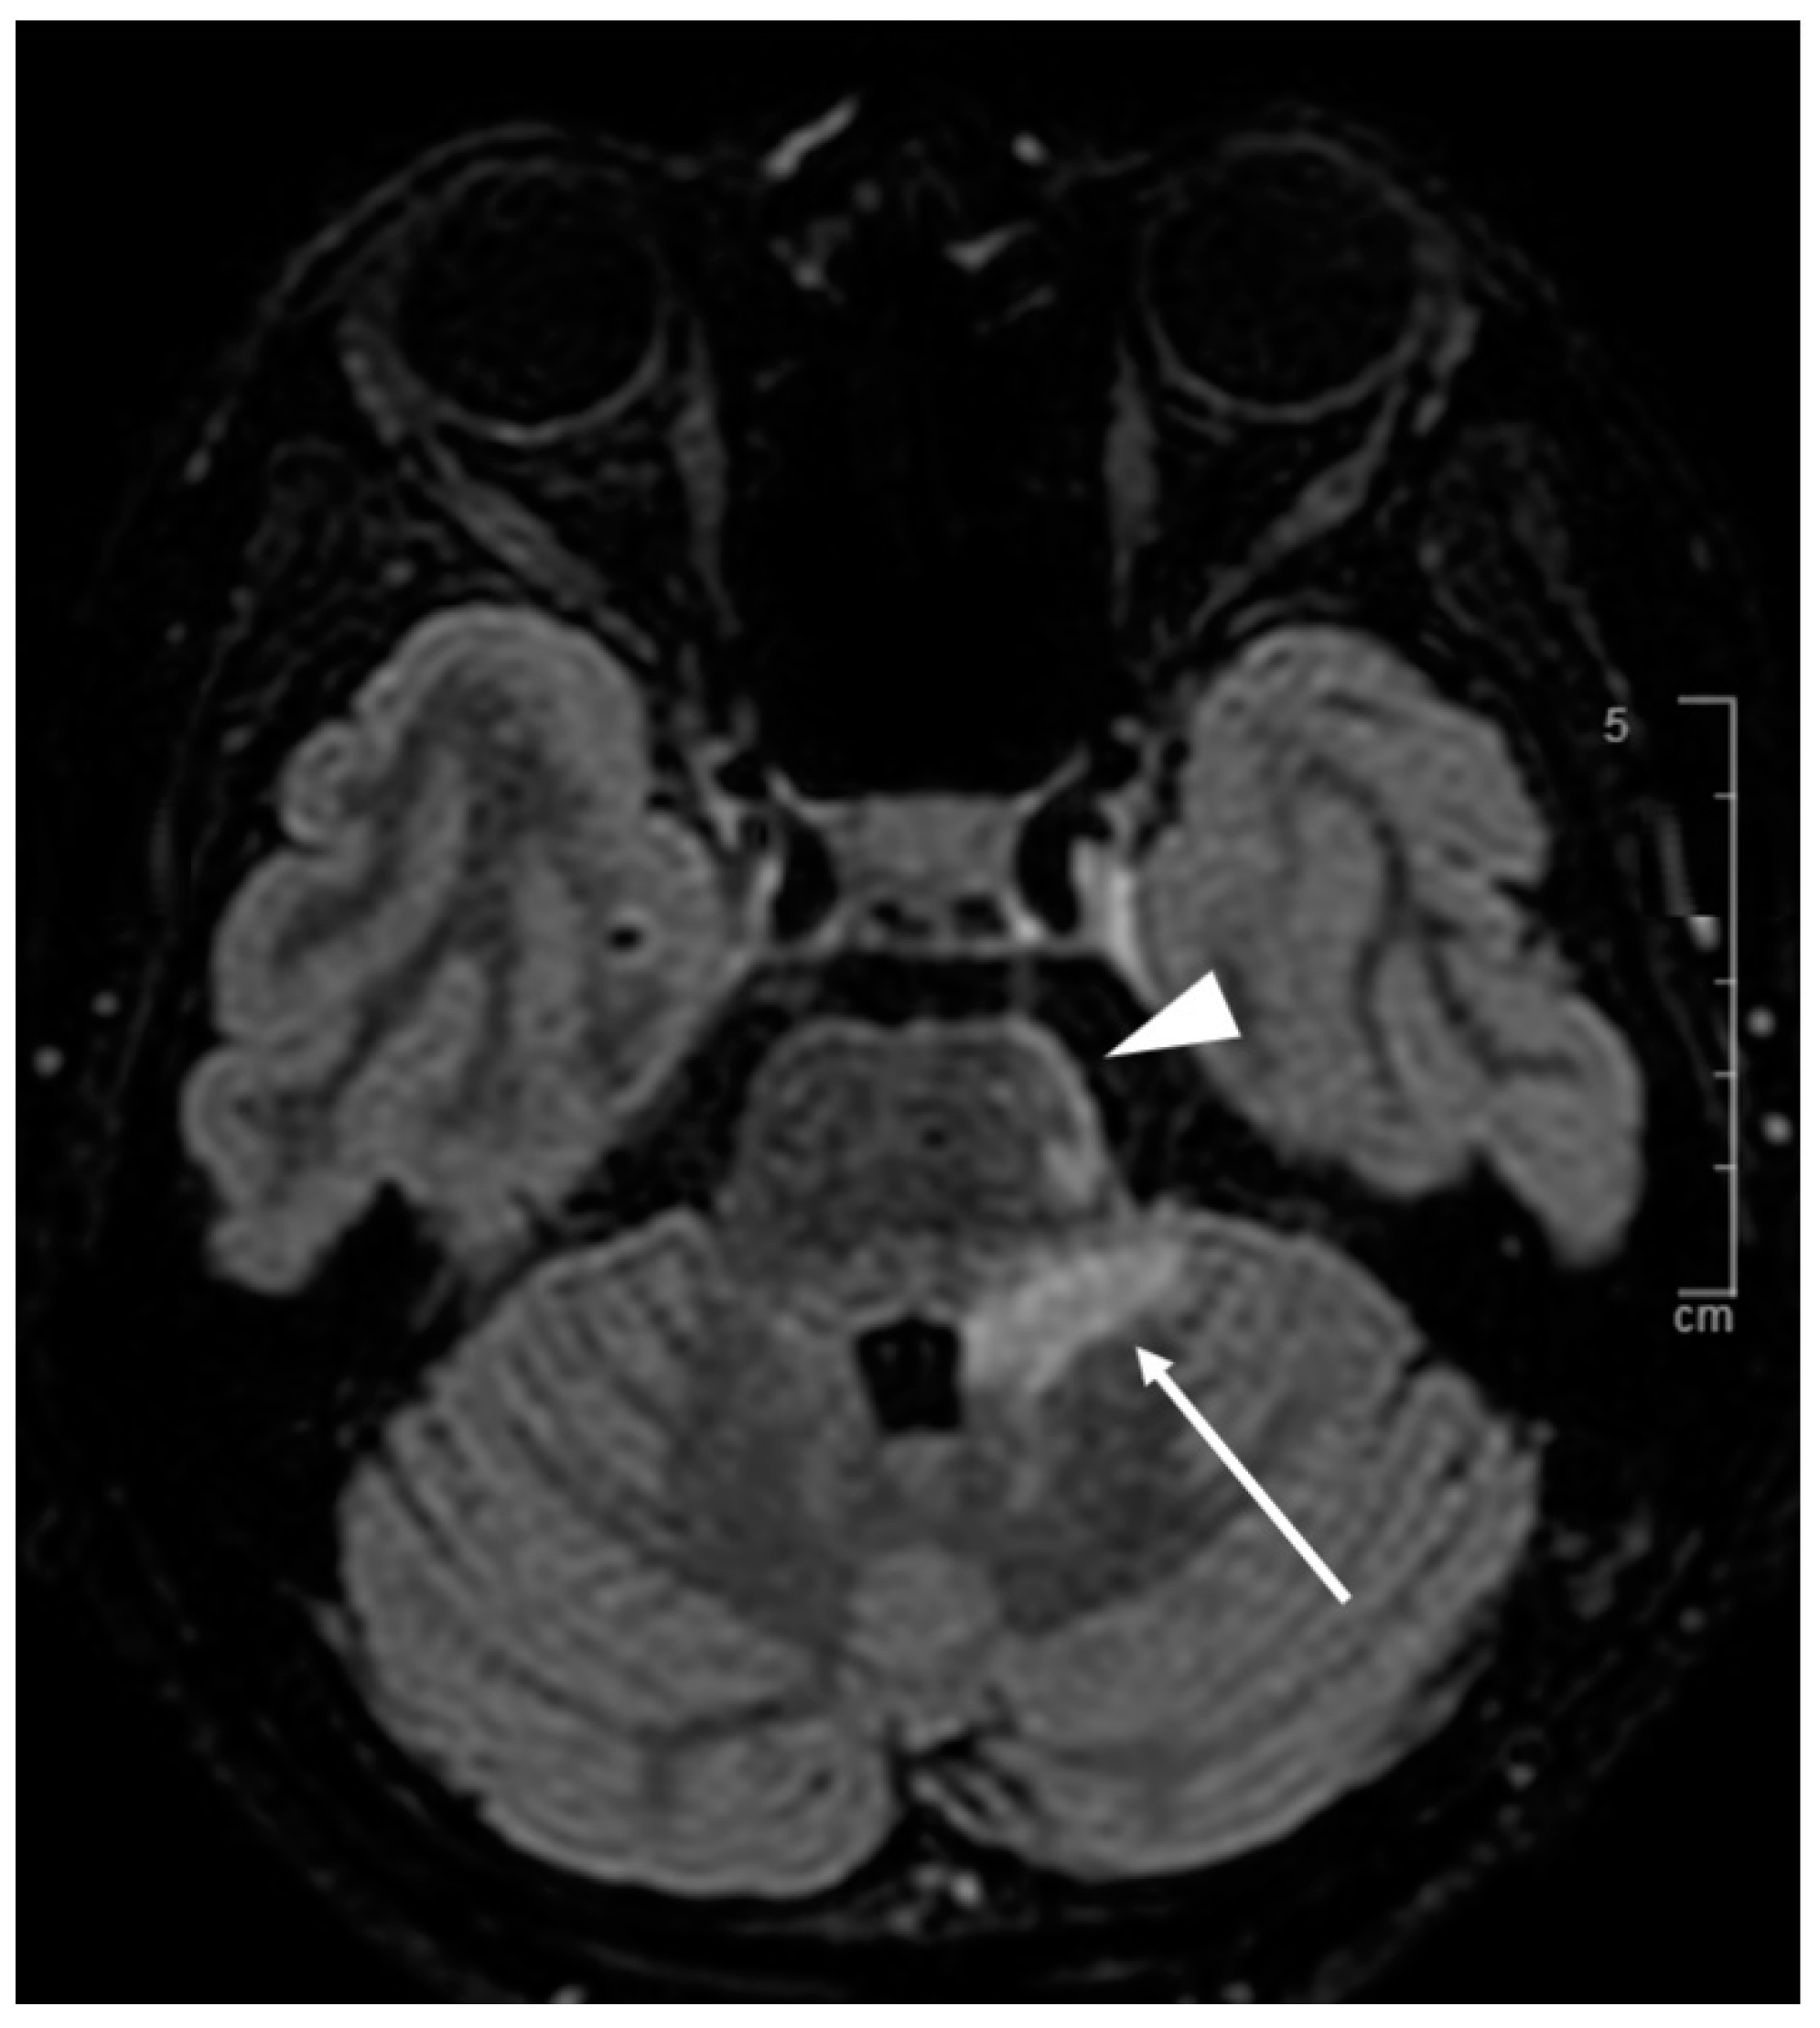

3.7.1. Case Description